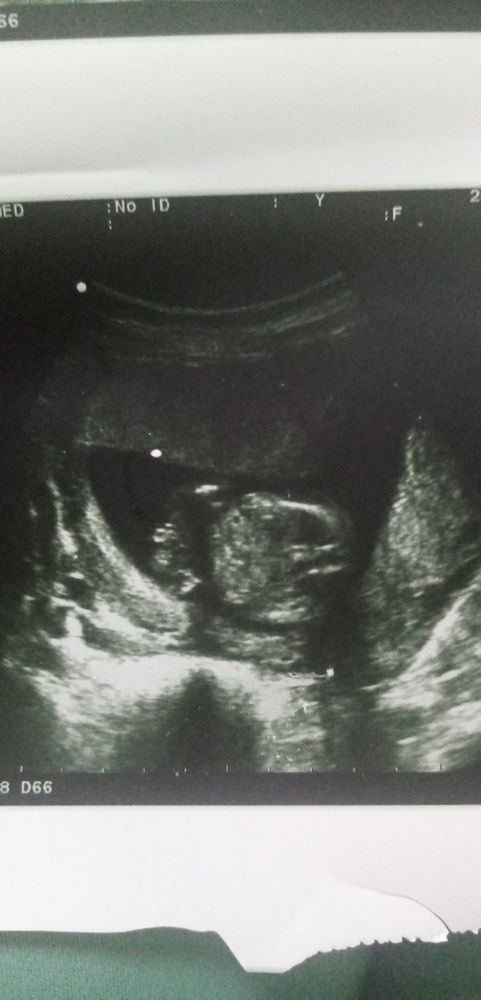

Пол в 17 недель. Ошибка?

Конкретно это фото нечёткое, по нему сложно судить. А так в теории в 18 недель УЗИ точнее, чем в 14, а на практике зависит от пряморукости и опыта узиста)

Мне кажется девочка 👧 видно прям "пирожок" 😁💗 у мальчиков так торчит🍆 на таком сроке ,что и не спутать 😄